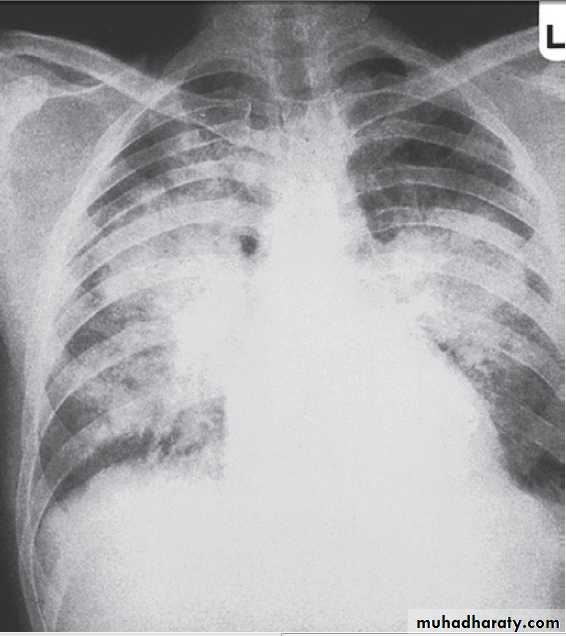

Pulmonary oedema in acute kidney injury. The appearances are indistinguishable from left ventricular failure but the heart size is usually normal. Blood pressure is often high.